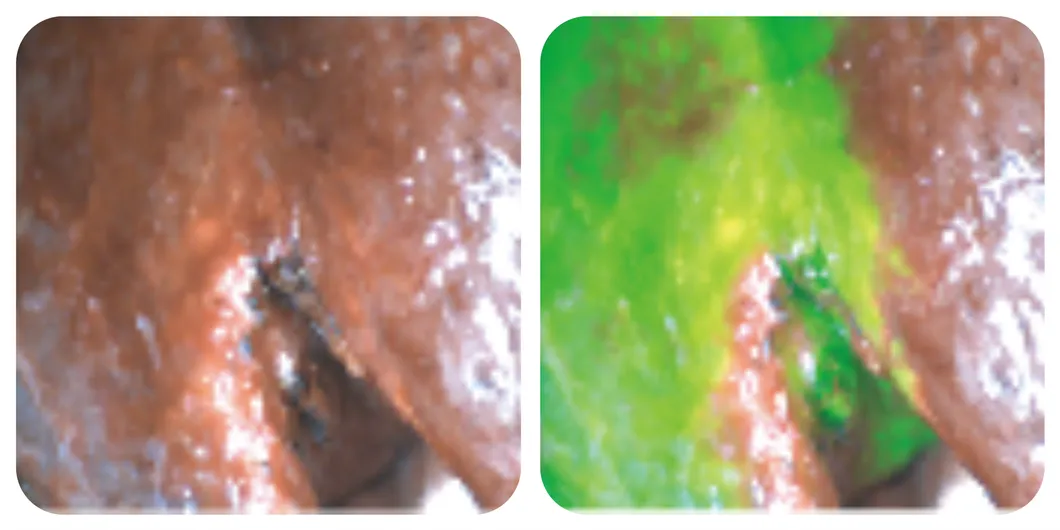

The Surgical Fluorescence Imaging System is a cutting-edge surgical guidance system employing a drug-device combination approach. Using Indocyanine Green (ICG) as a fluorescence probe, it utilizes ultra-high sensitivity to detect submillimeter-sized tumors. This provides surgeons with high-definition visible light, fluorescence imaging, and quantitative data essential for precise diagnostic information during tumor surgery.

It is ideal for real-time observation of tissues (tumor and margin tissue), blood supply (free skin flaps), lymph nodes (sentinel and regional), and anatomical structures (liver, gallbladder, lung segments). It optimizes surgical plans across multiple departments including Oral and Maxillofacial, Plastic/Reconstructive, Thyroid, Breast, Pediatric, and General Surgery.